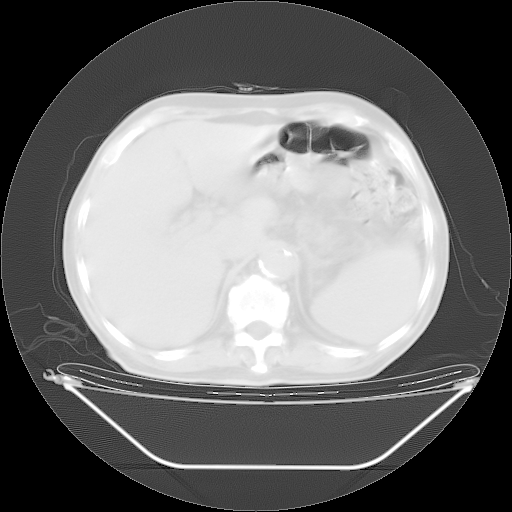

胸腹部CT,诊断意见:左上肺叶钙化灶、左侧胸膜局限性增厚并钙化、胆囊炎。描述部分肺组织呈磨玻璃样改变。

今天复查肺部CT,发现双肺广泛磨玻璃样改变。所以我把3月19日和5月9日相隔50天的肺部CT上传。请大家会诊。

5月9日肺部CT(在4月27日齐鲁医院肺部CT描述部分肺组织磨玻璃样改变,12天后肺组织广泛磨玻璃样改变)

大致读了系列胸部CT:纵隔窗无明显异常,肺窗:从4、27至今:主要是双肺中下野外带可见毛玻璃样改变,目前处于急性肺泡炎阶段,至于原因考虑1、结替组织或胶原血管性疾病所致?2、恶性疾病如恶组在肺部所致的表现或细支气管肺泡癌?3、药物或其它原因如肺蛋白沉着症所致肺泡炎目前不太可能?总之,明天就去请我院的呼吸科、感染科、血液科和临免专家会诊哈。